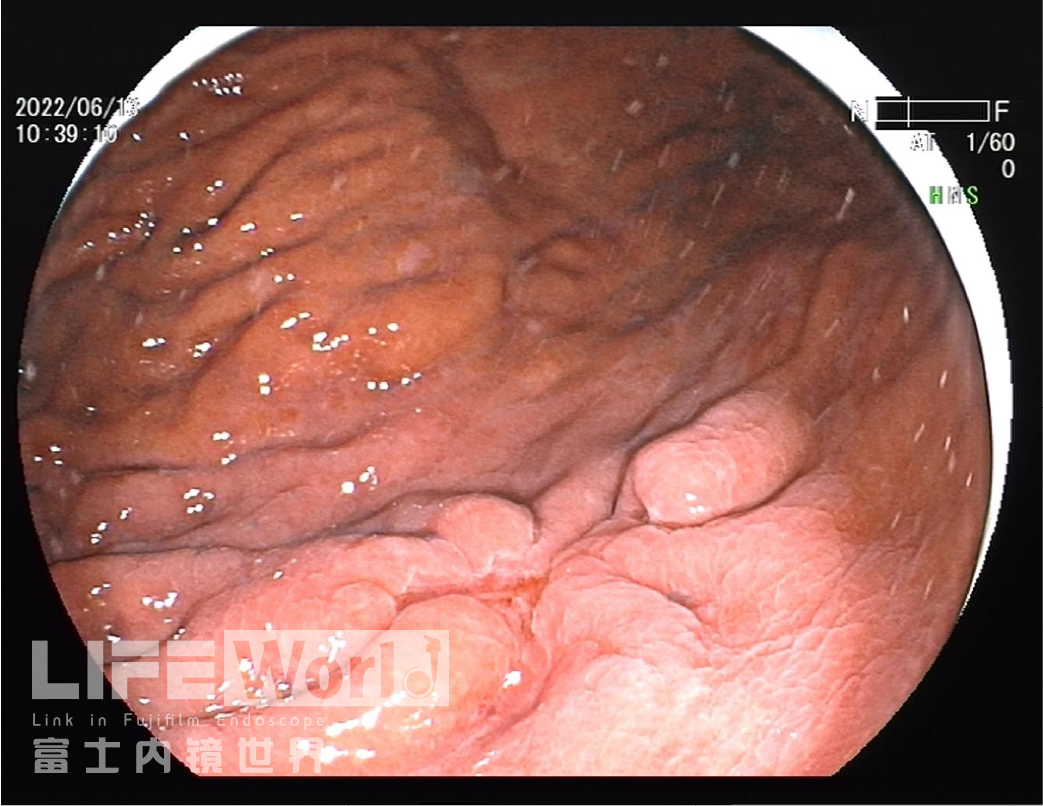

充气吸气后,可见病变凹陷处延展性欠佳,周围皱襞集中、中断。

除了黄圈内考虑为癌灶的病变发红,白圈内考虑为上皮内瘤变的病变也略发红。